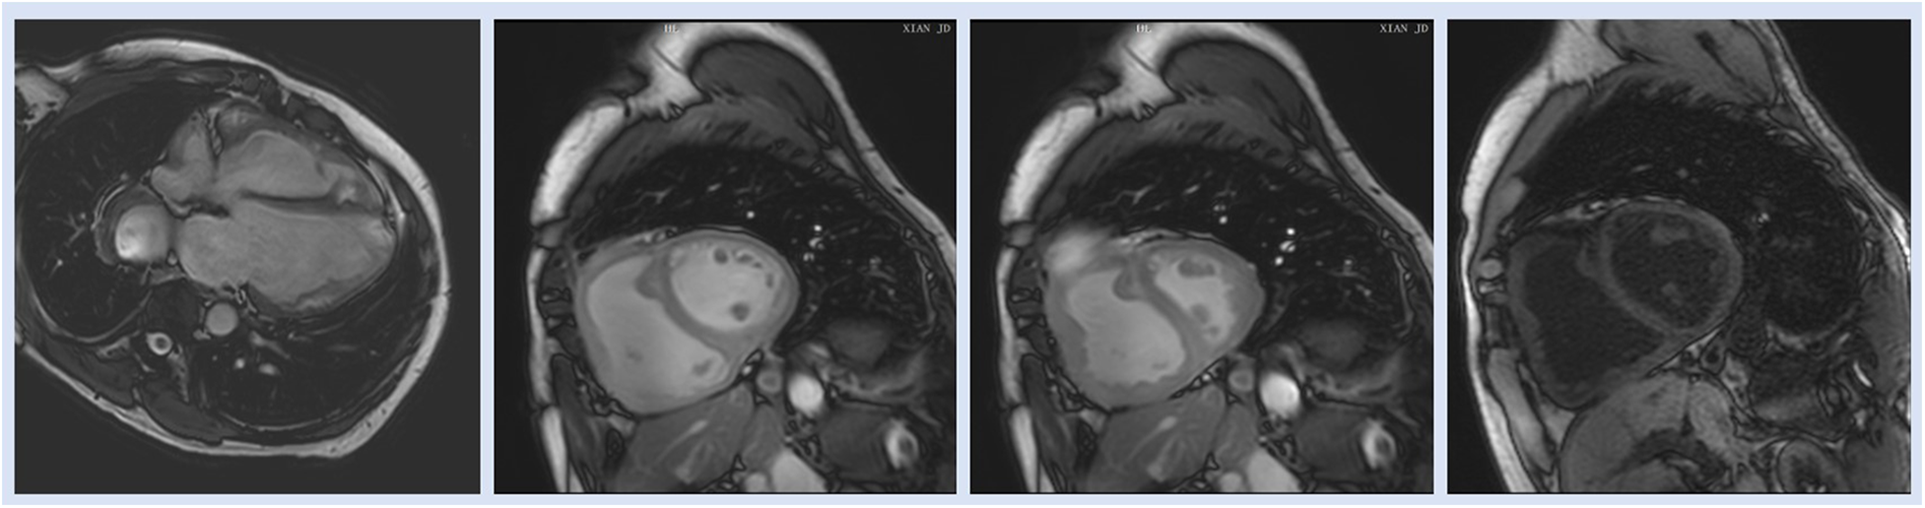

T1 mapping, a newly developed CMRI technique, measures native RV T1 based on pre- and postcontrast T1 timings to detect widespread myocardial anomalies (69). T1 mapping may be a useful tool for identifying fibrosis, which has recently been linked to both maladaptive responses that lead to increased diastolic stiffness and adaptive responses that prevent cardiomyocyte overstretch and preserve RV shape for optimal function (70). Similarly, in a case control study Ostenfeld et al. (17) demonstrated that despite a preserved global LV function, the LV function is affected in patients with PH. They found that LV atrioventricular plane displacement (AVPD) and corresponding longitudinal contribution to LV SV was lower in patients compared with controls. Interestingly, the decreased longitudinal contribution to LVSV was not seen in the RV, contrary to previous findings in RV volume overload (17) (Figure 4).

Figure 4

Representative images of cardiac magnetic resonance imaging in patient with PH.